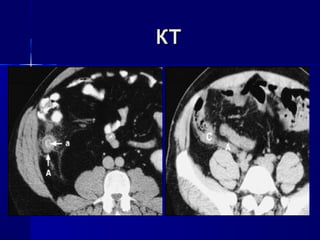

 КТКТ

КТКТ